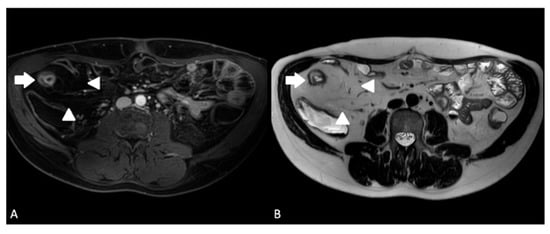

- Guglielmo, F.F.; Anupindi, S.A.; Fletcher, J.G.; Al-Hawary, M.M.; Dillman, J.R.; Grand, D.J.; Bruining, D.H.; Chatterji, M.; Darge, K.; Fidler, J.L.; et al. Small Bowel Crohn Disease at CT and MR Enterography: Imaging Atlas and Glossary of Terms. Radiographics 2020, 40, 354–375. [Google Scholar] [CrossRef] [PubMed]

- Sinha, R.; Verma, R.; Verma, S.; Rajesh, A. MR enterography of Crohn disease: Part 2, imaging and pathologic findings. AJR Am. J. Roentgenol. 2011, 197, 80–85. [Google Scholar] [CrossRef]

- Rimola, J.E. Cross-Sectional Imaging in Crohn’s Disease, 1st ed.; Springer International Publishing: Cham, Switzerland, 2019. [Google Scholar]